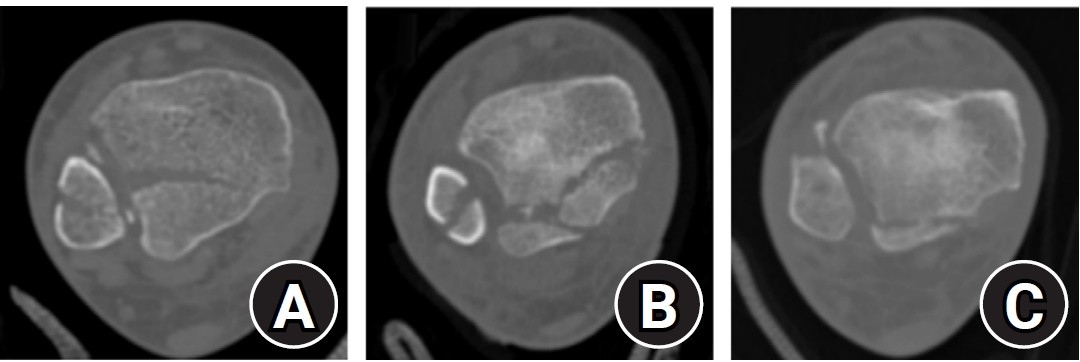

Posterior malleolar fracture morphology was classified according to the Haraguchi and Bartonicek systems (Figs. 2, 3) [19,20]. The peak height of the posterior malleolar fracture was measured as the vertical distance from the highest point of the distal tibial articular surface to the fracture apex in the sagittal plane (Fig. 4A). The articular surface area of the posterior malleolar fragment was calculated using the region of interest tool in a picture archiving and communication system (Maroview 5.4; INFINITT Healthcare) (Fig. 4B). All quantitative radiographic measurements were performed by two orthopedic surgeons; mean values were used. For categorical variables, disagreements were resolved by consensus.

The mean vertical peak height of the posterior malleolar fracture was greater in the ≥4.5 cm group (21.0 mm) than in the <4.5 cm group (15.2 mm; P=0.002). The articular surface area of the posterior malleolar fragment at the distal tibial articular surface was also significantly larger in the ≥4.5 cm group (242.2 mm2 vs. 140.7 mm2; P<0.001). The fragment involved 19.2% of the tibial plafond in the ≥4.5 cm group compared to 12.0% in the <4.5 cm group, indicating significantly greater absolute size and articular involvement in fibular fracture extending ≥4.5 cm proximal to the ankle joint (P<0.001). These results suggest that posterior malleolar fragments are larger in the ≥4.5 cm group.

Fig. 4.

(A) Peak height (a) of the posterior malleolar fracture is defined as the vertical distance from the highest point of the distal tibial articular plafond to the apex of the posterior malleolar fragment on the sagittal plane. (B) The articular surface area (mm2) of the posterior malleolar fracture fragment (b) was measured using the region of interest tool in a picture archiving and communication system. Articular involvement (%) was calculated as the ratio of the fractured area (b) to the total tibial plafond articular surface area (b+c).

Fig. 4. (A) Peak height (a) of the posterior malleolar fracture is defined as the vertical distance from the highest point of the distal tibial articular plafond to the apex of the posterior malleolar fragment on the sagittal plane. (B) The articular surface area (mm2) of the posterior malleolar fracture fragment (b) was measured using the region of interest tool in a picture archiving and communication system. Articular involvement (%) was calculated as the ratio of the fractured area (b) to the total tibial plafond articular surface area (b+c).